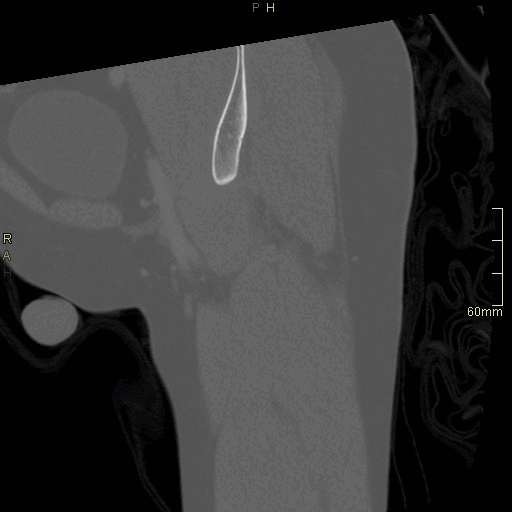

CT Hip Contrast- Soft tissue window (sagittal)

CT Hip Contrast- Bone window (sagittal)

CT Hip Non Contrast- Bone window (sagittal)